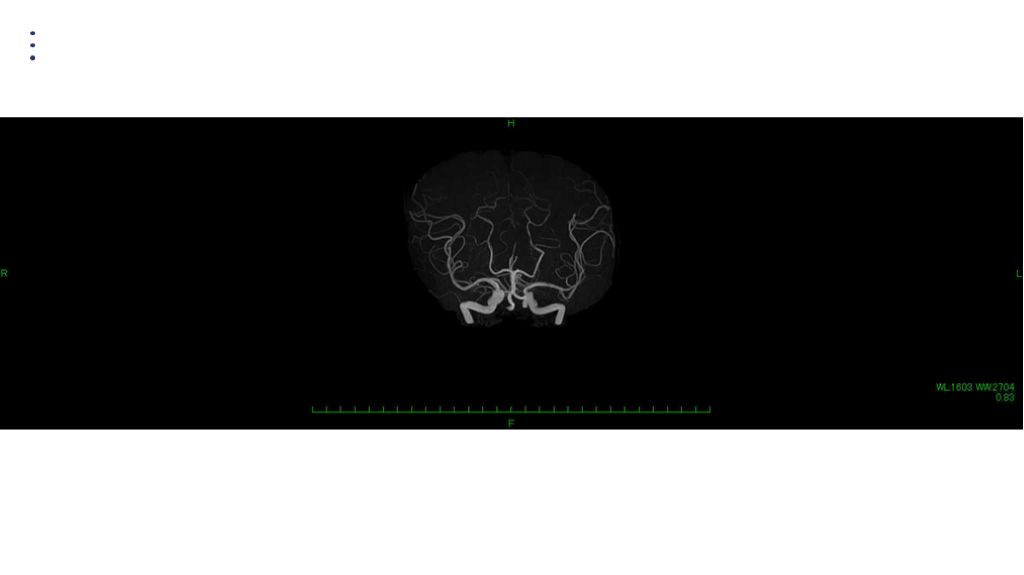

画像 所見 DAY 30 MRA 改善